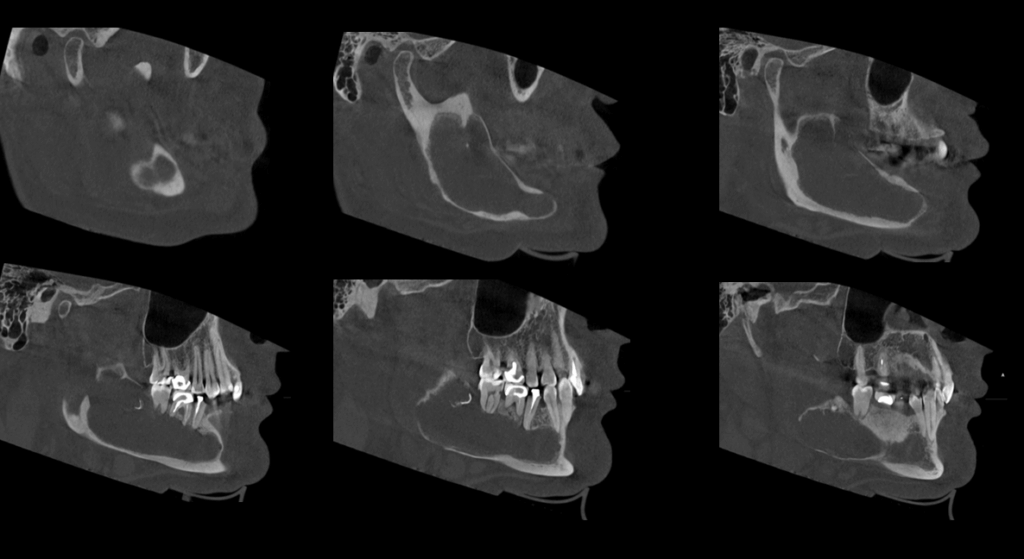

A la evaluación de la tomografía volumétrica (cone beam) bimaxilar en los cortes axiales (Figura 2), coronales, (Figura 3) y tangenciales (Figura 4) se observa imagen isodensa irregular, ubicado en cuerpo, ángulo y rama ascendente mandibular de lado derecho, que se extiende desde zona periapical mesial de pieza 44, hasta tercio medio de rama mandibular, y desde tercio superior (próximo a base de apófisis coronoides) hasta basal mandibular ocasionando expansión de tablas ósea, adelgazamiento de corticales y pérdida de continuidad de tabla vestibular en zona de pieza 45 y de tabla ósea lingual a en zona de pieza 46, 48 y rama mandibular. Además de producir el desplazamiento caudal y borramiento parcial de las corticales del canal mandibular; así mismo, se observó reacción periostal en tabla ósea vestibular (próxima a escotadura sigmoidea), ángulo mandibular y en basal mandibular de zona antegonial. Se pudo evidenciar tambien a la pieza 48 incluida y con reabsorción severa 48 dejando solo restos de esmalte.

CORTES TANGENCIALES